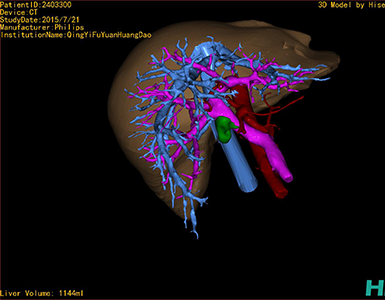

术前三维重建及手术方案设计:

将0.625mm双源薄层CT资料的静脉期和动脉期Dicom格式文件导入海信CAS系统。

通过调节窗宽窗位调整CT序号,对肿瘤,肝实质,胆囊,下腔静脉,肿瘤,肝动脉、门静脉及肝静脉等进行三维重建;系统自动计算肿瘤体积和肝脏体积。

模拟手术操作,自动计算切除肿瘤体积。肝脏体积为1096ml,胰腺肿瘤体积为115.5ml,通过比对12-13岁正常肝脏体积为1116.86±158.78 ml,通过术前模拟手术,精准判断切除后肝脏体积无明显变化,避免肝衰竭发生。

术前三维重建:

重建图片